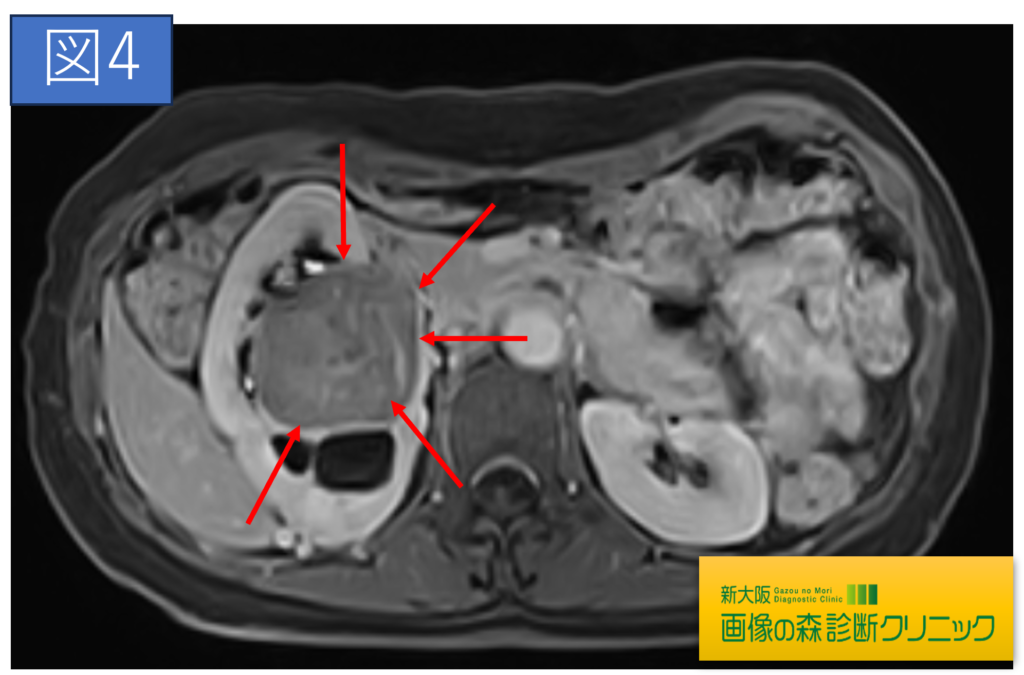

腎臓造影MRI画像(横断像)

症例画像から図1~図4は腎臓癌の画像です。矢印は腎臓癌を示します。図1・図2はDWIBS_MRIの画像です。DWIBS_MRIは、頚部~骨盤までの広範囲の癌検索を目的としており、癌の疑いのある臓器はこの画像の場合、黒く描出されます。(脳や脾臓も黒く見えますが、これらの部位は他の部位より黒く描出されやすいので、その他の撮影画像と比較することで評価されます)図3・図4は造影剤を使用し腎臓に焦点をあて検査した画像です。